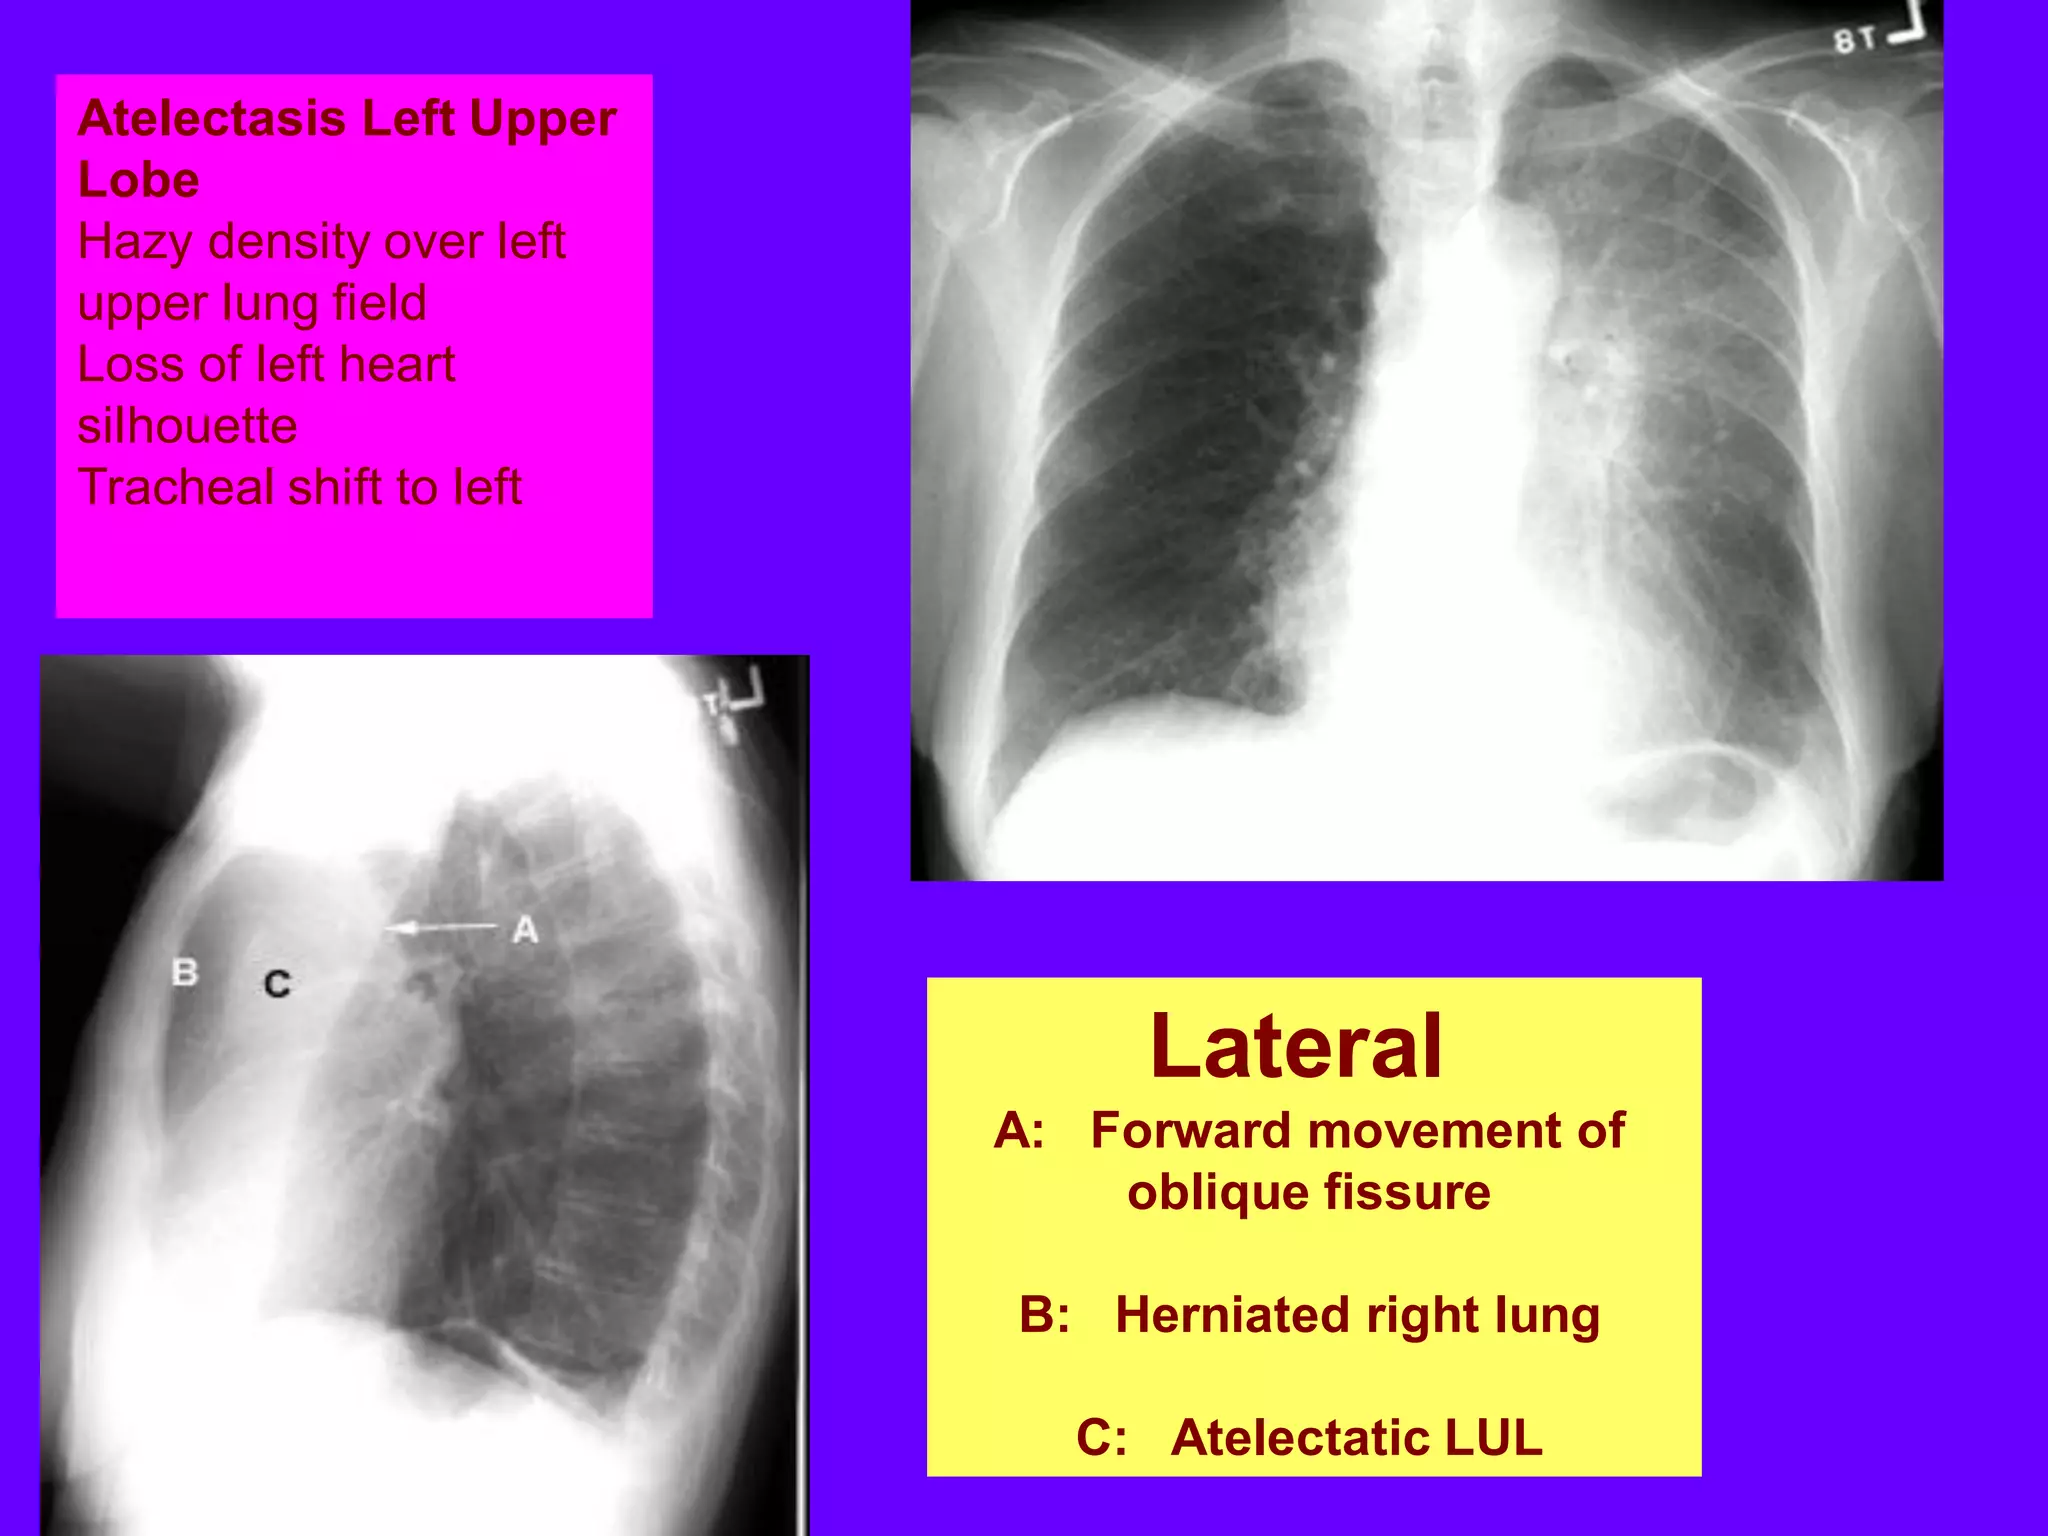

Atelectasis Left Upper

Lobe

Hazy density over left

upper lung field

Loss of left heart

silhouette

Tracheal shift to left

Lateral

A: Forward movement of

oblique fissure

B: Herniated right lung

C: Atelectatic LUL